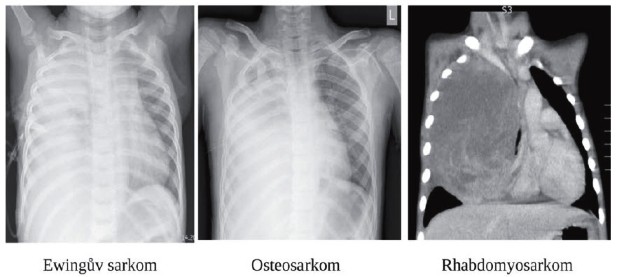

Sarkomy primárně postihující bronchy a dýchací cesty jsou u mladé generace vzácné, výrazně častější jsou sarkomy vyrůstající z hrudní stěny a propagující se intrathorakálně (obr č. 2).

Plíce jsou u dětí a mladých lidí velmi častou lokalizací metastatického rozsevu. Typ nádoru zásadně ovlivňuje věk. U malých dětí nejčastěji do plic metastazuje Wilmsův nádor, hepatoblastom, rhabdomyosarkom nebo neuroblastom. U dospívajících pacientů jsou plicní metastázy nejčastější u sarkomů kostí a měkkých tkání. U dospívajících chlapců je vždy nutno myslet na germinální nádor varlete jako o vůbec nejčastější malignitu v tomto věku. Zobrazovací vyšetření opět ne vždy dá jednoznačnou odpověď (obr č. 3).